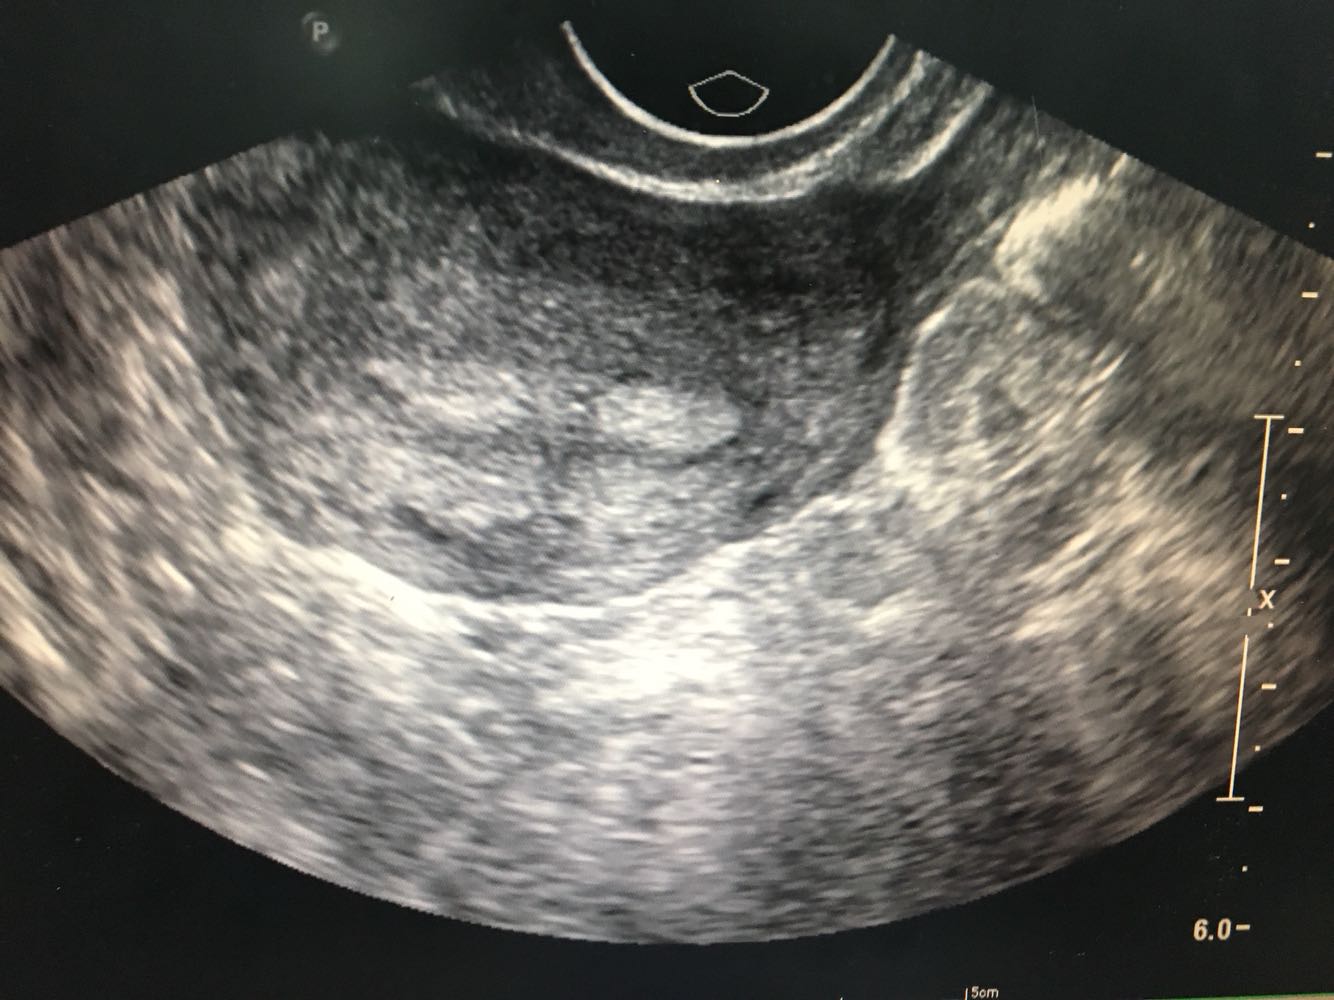

1.患者,女,35岁     2.主诉:人流后经量减少伴痛经7月余 3.现病史:0-0- 2-0,初潮14岁,既往5/25,经量中等,无痛经。患者于2016年12月行人工流产术,术后1月月经正常来潮,2017年1月起出现明显经量减少,经期缩短伴下腹坠痛,自行服用中药调理(具体药物不明),未见明显好转。2017年4月就诊外院,B超诊断为宫颈粘连(报告未见),当时未予特殊处理。患者经量仍有减少,经期缩短至1天,腹痛症状逐渐加重,无腹泻,无恶心呕吐,无畏寒发热等不适。遂就诊我院B超示子宫内膜回声不均匀,宫腔部分粘连可能;小型子宫肌瘤;盆腔积液;右附件系膜囊肿。现患者有生育要求,为寻求进一步治疗,拟“人工流产后宫腔粘连”收治入院。病程中患者无异常阴道流血流液,无经期间出血,无发热,无恶心呕吐。

诊断: 流产后宫腔粘连(可能);子宫平滑肌瘤(小型) 诊疗方案:患者入院后完善各项检查,麻醉下行宫腔镜下宫腔粘连分解+刮宫术,术中见:宫颈管形态正常,宫腔上1/3宫底处粘连,左右两侧壁膜状轻度粘连,双侧输卵管未见。以剪刀剪开宫底处粘连使宫底处展平,暴露双侧输卵管开口清晰,剪除左右两侧壁膜状粘连带,使宫腔恢复正常形态。刮匙沿宫腔四壁轻柔搔刮,刮出少量内膜送病理。手术顺利,术后给予抗炎治疗,观察阴道出血少,患者生命体征平稳。